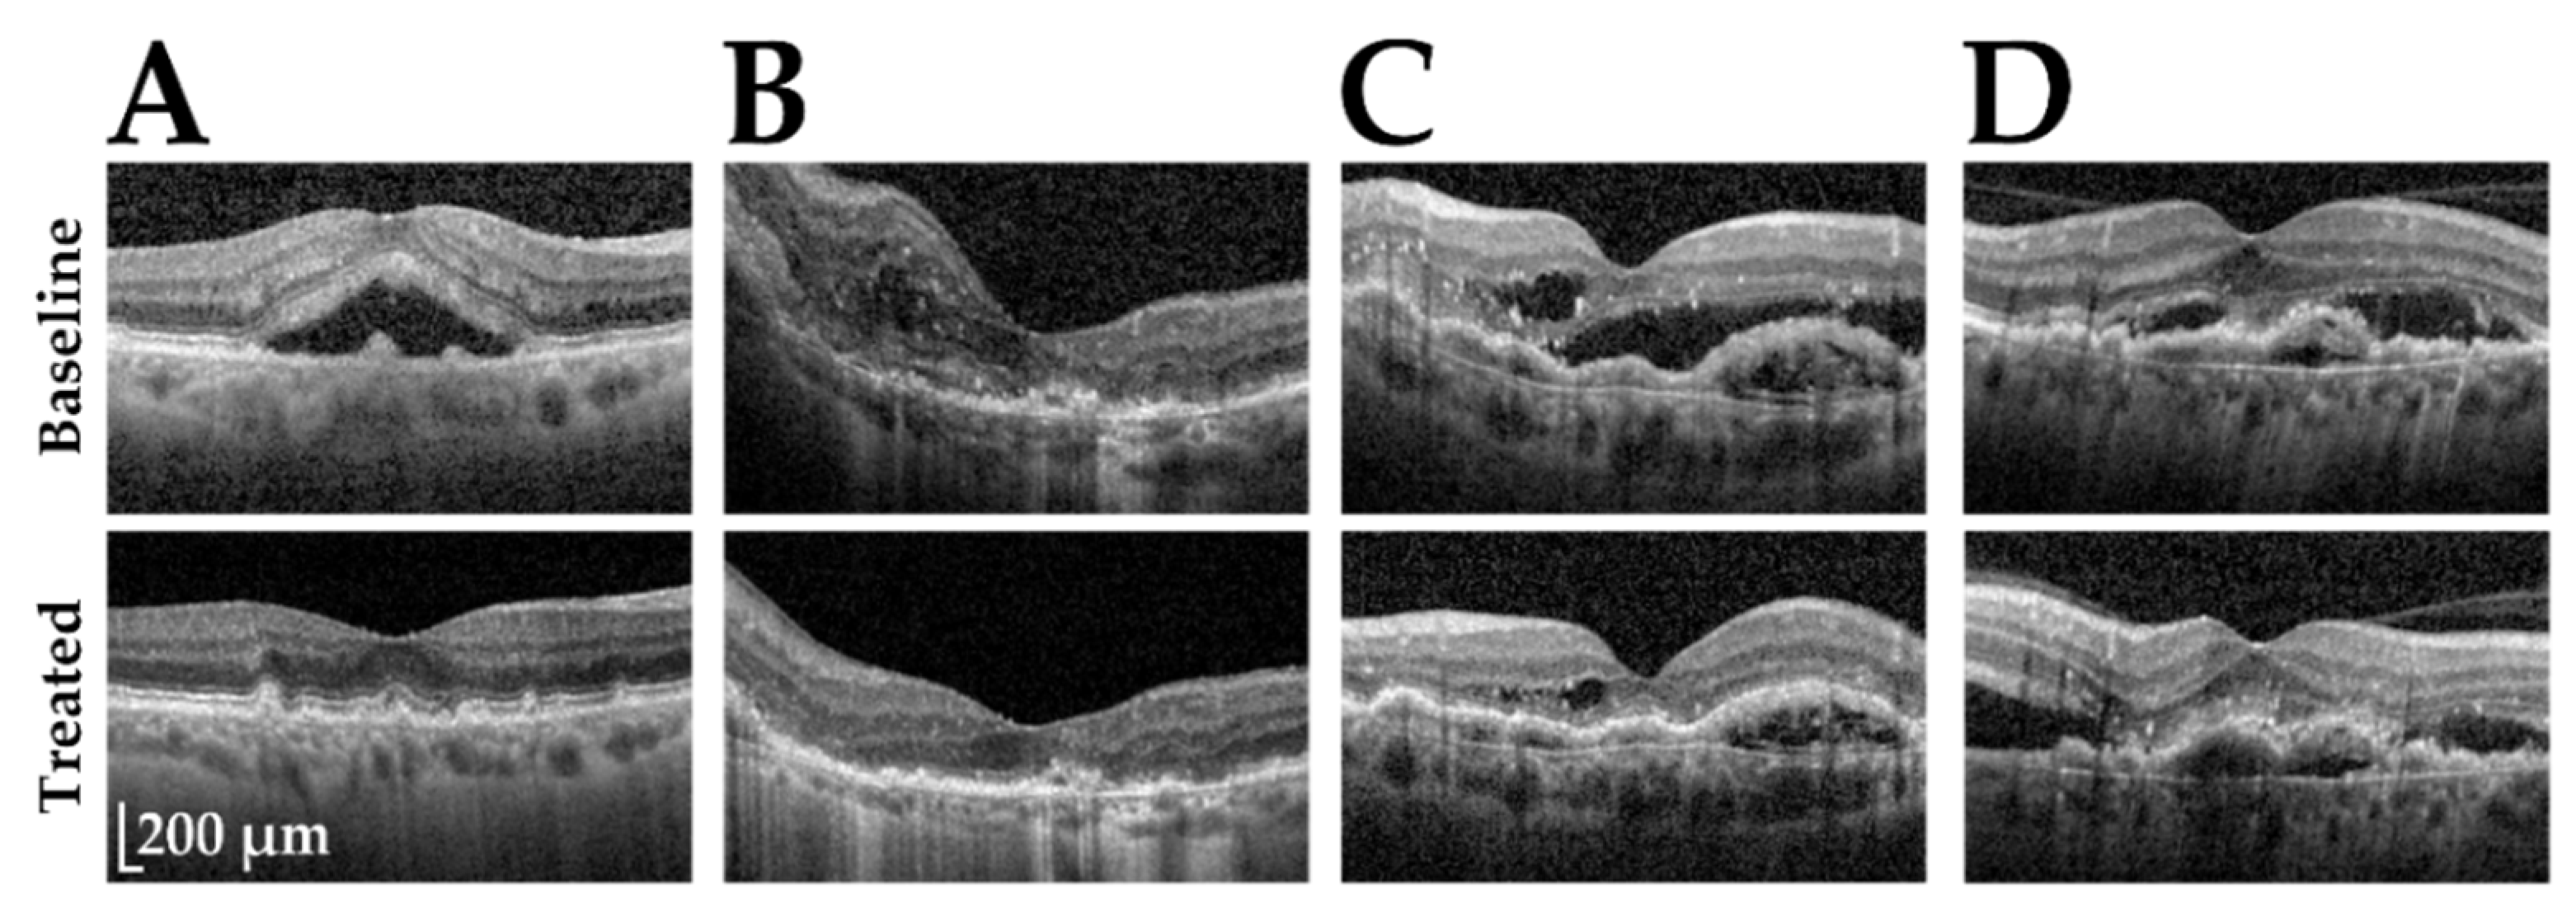

2.4. Definition of Treatment Response